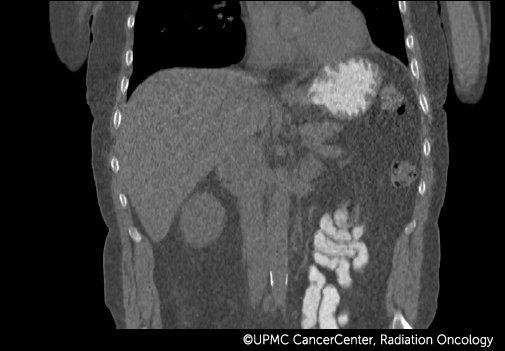

4D PET-CT combines positron emission tomography (PET) with computed tomography (CT) to take advantage of these faster, more accurate technologies.

- Creates the most complete and accurate imaging data on your tumor and critical organs.

- Allows your oncologist to see how your tumor moves with breathing and other normal body motions.

By understanding the functional and material aspects of the tumor, your radiation oncologist can conclude which parts of the tumor need more (or less) radiation for more effective treatment.

4D PET and 4D CT images fuse together and show:

- How your tumor moves.

- How your breathing affects the tumor.

- How movement of nearby organs affects the tumor.